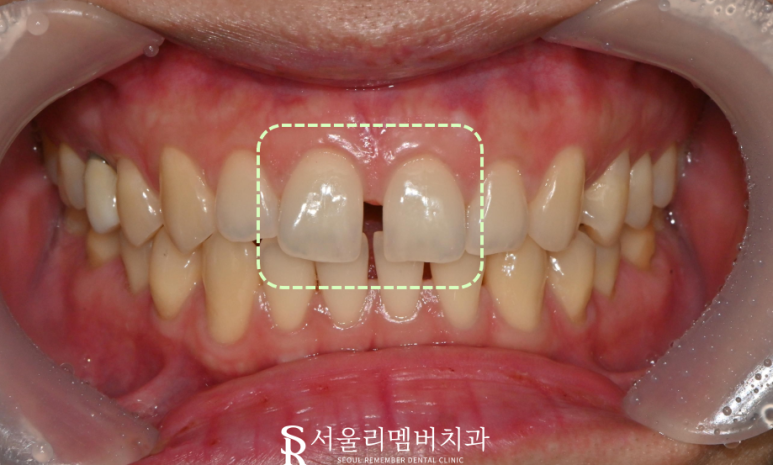

언뜻 보기에도,

이가 벌어진 것을 볼 수 있었습니다.

그래서 신대방 치과 에서

사진을 찍어 구강검진을

진행하게 되었습니다.

치료 기간 : 2024. 12. 30

사진에서 볼 수 있듯

앞니 사이가 벌어진 것을

알 수 있었습니다.